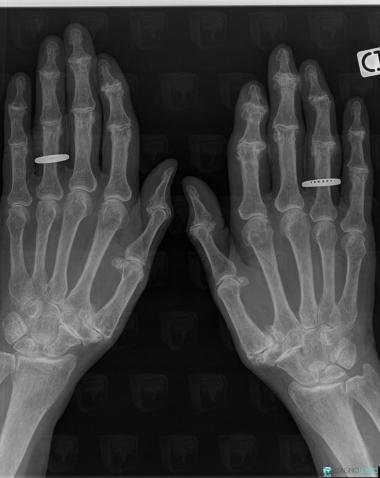

The images below illustrate this case for diagnoses Degenerative joint disease, CPPD, Chondrocalcinosis, for the modalities (X rays)

Here is the specific information in the key image above:

- Diagnosis CPPD, Location(s) Mediocarpal joint, with gamuts

- Diagnosis Degenerative joint disease, Location(s) Phalanx / Sesamoid bones - Hand, with gamuts Phalangeal osteolytic lesionInterphalangeal joint - Hand, with gamuts

- Diagnosis Chondrocalcinosis, Location(s) Metacarpophalangeal joints, with gamuts